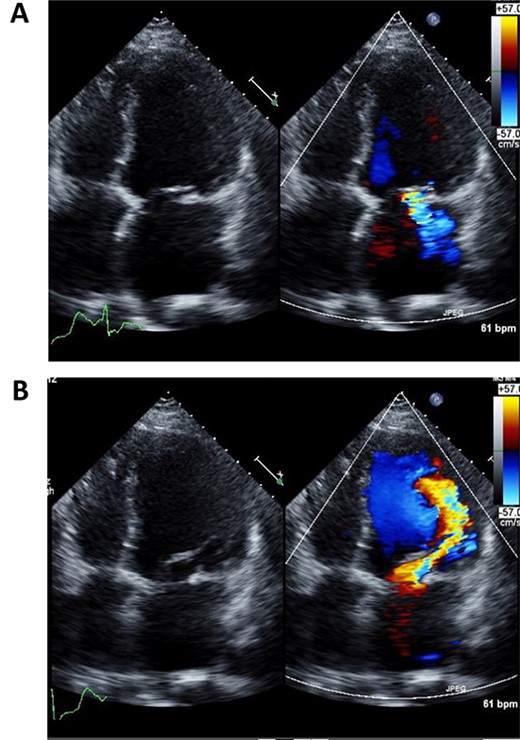

Immediately after the operation, echocardiography revealed improved cardiac function: left ventricular ejection fraction of 37% (Fig. 3A and B). Postoperative course was uneventful and the patient was discharged 2 weeks post operation. Fourth year follow-up revealed further improvement in cardiac function; left ventricular ejection fraction of 42%. The patient continues to do well with NYHA class I status.

Postoperative echocardiography of left ventricle in systolic (A) and diastolic (B) phases.